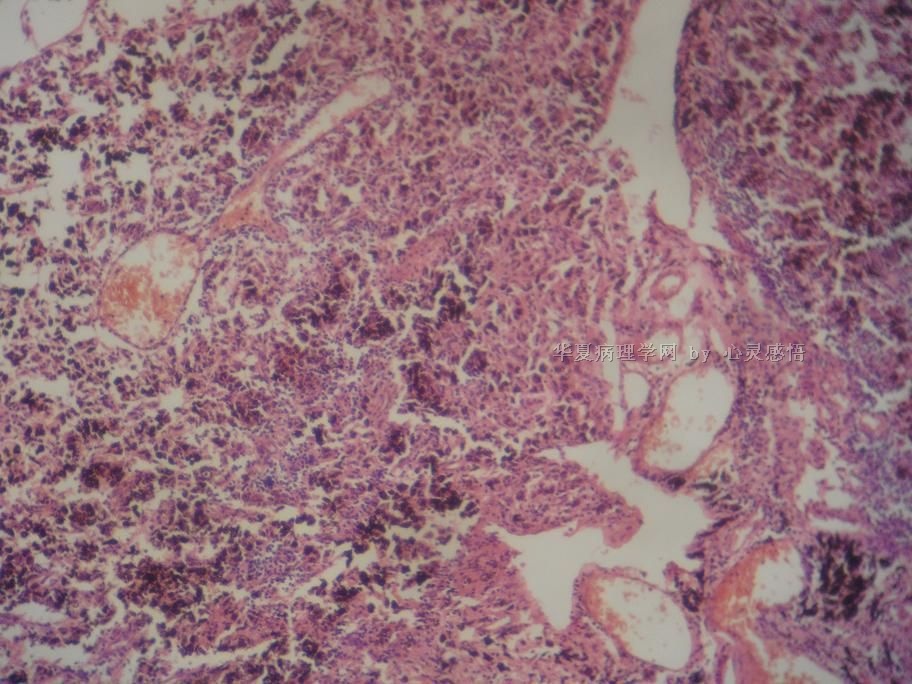

• 食道癌,淋巴结有没有转移,谢谢。图2

图2

1-6图是鳞癌。7-22图片无癌。

淋巴结没有转移

本帖最后由 于 2010-11-17 20:19:00 编辑  图14,19有转移

没有转移。

请教楼主;图片19是淋巴结吗?如果是应该是有癌转移!

没有转移,食道旁的淋巴结和肺旁的淋巴结相似,含有吞噬细胞。